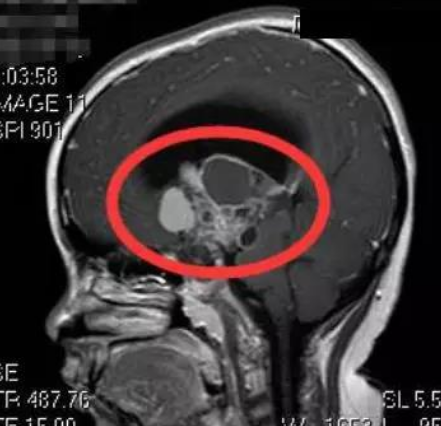

颅咽管瘤全切复发概率?颅咽管瘤是比较常见的良性神经系统肿瘤,起源于蝶鞍的前缘,主要累及蝶鞍和鞍上间隙。它们很少转移,但具有局部侵袭性(通常是下丘脑)。

对于颅咽管瘤的治疗,手术切除是首要选择。尽管颅咽管瘤在组织学上是良性的,但颅咽管瘤可以从手术时残留下来的肿瘤宏观上再生。所以颅咽管瘤是神经外科界公认的“难缠”肿瘤。另外由于颅咽管瘤生长位置较深,手术全切除率低,导致其具有高复发以及无瘤长期生存率低的特性。虽然颅咽管瘤全切后,理论上不再复发,但是往往表面上完全切除后也可以再生。

那么,颅咽管瘤全切复发概率是多少呢?一般的良性肿瘤只要通过手术全切,基本可以说是完全治好,术后不再复发。但颅咽管瘤通过临床观察,全切患者仍然存在复发率,随访五年左右复发概率为10%左右。具体复发概率主要取决于手术治疗的效果和肿瘤本身的生长潜力。颅咽管瘤尽管全切也有可能复发,但是与次全切除或部分切除相比,完全切除的复发风险要小得多。其他复发因素包括术后的随访时间和病人的年龄,儿童比成人更容易复发。

颅咽管瘤全切复发概率?虽然颅咽管瘤完全切除并不能确定异位或主要部位不会复发,但手术全切后的颅咽管瘤预后明显更好。但颅咽管瘤较常见的部位是在鞍区,属于颅脑的中心地带,位置深,并且周围有视神经、颈内动脉、大脑前动脉、垂体、下丘脑等主要结构,而且颅咽管瘤常常与下丘脑粘连。在手术过程中如果视神经受损,会导致视力下降、甚至失明。颈内动脉或大脑前动脉受损,会造成大出血,危及生命。下丘脑、垂体受损会出现垂体功能低下、内分泌紊乱,轻者造成病人体质差、抵抗力差,严重者也会造成生命危险。颅咽管瘤的手术难点在于既要尽可能的完全切除肿瘤,防止肿瘤复发,又要避免手术对肿瘤周围的重要结构造成损害。所以颅咽管瘤手术全切难度是高的,其全切除的比例也并不高,不同医院、不同医生均存在差别。对于颅咽管瘤手术,国际神经外科学院院长、国际脑膜瘤协会前主席美国William Couldwell教授、国际神经外科学会联合会(WFNS)内镜委员会前主席Henry W.S. Schroeder教授、神经内镜及颅底手术的国际高手Sebastien Froelich 教授是擅长的,他们可以根据不同分型的颅咽管瘤,在不同入路的优势和使用不同入路的代价之间进行权衡,进而选择更佳预后的入路。